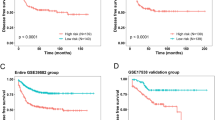

Model analysis and validation

The six lncRNAs in Table 3 were subjected to survival analysis in the training, testing, and total set (See Supplementary Table S1, Additional File 1). The risk scores of the samples in these three sets were calculated as follows: risk score = (0.0126948 × expression level of ENSG00000259347.4) + (0.0011064 × expression level of ENSG00000228437.4) + (0.0018182 × expression level of ENSG00000253405.1) + (− 0.0342018 × expression level of ENSG00000271797.1)+ (0.0061149 × expression level of ENSG00000166770.9) + (− 0.0299009 × expression level of ENSG00000264016.2). We first analyzed the distribution of risk scores and the relationship between risk level and overall survival (Fig. 7a–f). From the scatter plot (Fig. 7d–f), it is found that the risk level can significantly fit the overall survival of colon cancer patients in the training, testing, and total set. Then, three groups of Kaplan-Meier (KM) survival curves were constructed, as shown in Fig. 7g–i. It can be found that these six lncRNAs can clearly distinguish the high and low levels of the survival rate.

The risk score distribution, sample survival time, and Kaplan-Meier (KM) curve in the training, testing, and total set. a The risk score distribution in the training set. b The risk score distribution in the testing set. c The risk score distribution in the total set. d The sample survival time in the training set. e The sample survival time in the testing set. f The sample survival time in the total set. g The KM curve in the training set. h The KM curve in the testing set. i The KM curve in the total set

In order to further analyze and validate our prognostic model, we obtained six sample sets (early-stage samples in the training set, late-stage samples in the training set, early-stage samples in the testing set, late-stage samples in the testing set, early-stage samples in the total set, and late-stage samples in the total set) through collecting the colon cancer samples by their stages. Among them, samples from stage I/II belong to the early-stage group and samples from stage III/IV belong to the late-stage group. Then, we performed survival analysis on these six sets (Fig. 8). The results show that our model has good prognostic performance in both the early-stage and late-stage groups. We also analyzed the risk score distribution and overall survival of the samples in these 6 sets (See Supplementary Figure S1, Additional File 1). We found that samples with high risk levels were more likely to die than those with low risk levels in these sets, which is consistent with the expected results.

The Kaplan-Meier (KM) curves of early-stage (I/II) and late-stage (III/IV) samples. a The KM curve of early-stage samples in the training set. b The KM curve of early-stage samples in the testing set. c The KM curve of early-stage samples in the total set. d The KM curve of late-stage samples in the training set. e The KM curve of late-stage samples in the testing set. f The KM curve of late-stage samples in the total set